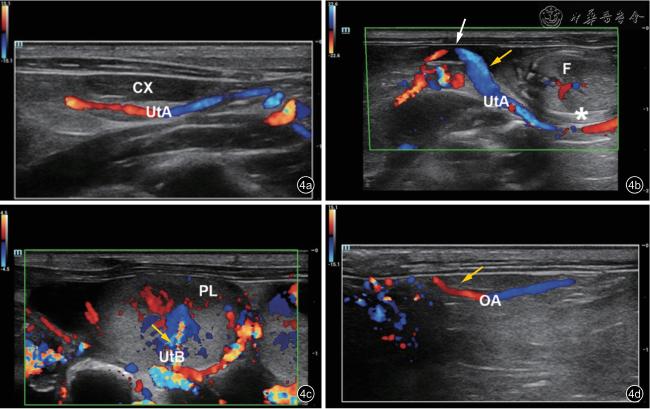

2. 研究方法:将3%戊巴比妥钠注射液(剂量50 mg/kg)注射入孕鼠腹部,使其深度麻醉后放置于操作台上。用剃毛器剃净孕鼠腹部绒毛,涂少量耦合剂并放置超声凝胶贴片。调整超声探头的角度及深度,在下腹部横切面显示宫颈(图1),转动探头分别调整至孕鼠双侧子宫体长轴方向,可见多个妊娠囊在双侧子宫体内依次呈串珠样相邻排列(图2),分为膨大部及缩细部:膨大部内见妊娠囊、胎鼠、胎盘、羊水;膨大部之间为环状缩细部(图3)。打开彩色多普勒成像,调整速度标尺约4.5 cm/s,增益设置约为50 dB,扫查孕鼠子宫胎盘循环:孕鼠UtA 起自髂内动脉的分支膀胱上动脉,自宫体宫颈交界处转向头侧,于子宫内侧缘沿宫体轮廓弯曲走行(图4a、4b),沿途发出数个子宫动脉分支(uterine artery branches,UtB)向胎盘内延伸(图4c);卵巢动脉(ovarian artery,OA)在肾动脉稍下方自腹主动脉发出,分为输卵管支、卵巢支及子宫支(图4d)。在自宫颈向上的第一、第二、第三和第四妊娠囊旁测量UtA 多普勒频谱,命名为UtA-1、UtA-2、UtA-3 和UtA-4,于第四妊娠囊旁测量UtB 多普勒频谱(图3);于OA 中段测量OA 频谱。测量部位选取上述血管走行较平直段,超声入射角度尽可能接近0°不得超过45°,取样门大小保持在0.3 ~ 0.5 mm 之间。至少获得3个及以上完整清晰的频谱时,固定图像,测量收缩期峰值流速(peak systolic velocity,PSV)、舒张末期流速(end diastolic velocity,EDV)、收缩期峰值流速与舒张末期流速比值(PSV/EDV,S/D)、阻力指数(resistance index,RI)、搏动指数(pulse index,PI)(图5)。每个部位分别测量2 次并取平均值。

注:CX 为宫颈,UtA 为子宫动脉,PL 为胎盘,UtB 为子宫动脉分支,OA 为卵巢动脉

图4 孕鼠子宫动脉各分段及卵巢动脉彩色多普勒超声图像。黄色箭头示测量点;图a:子宫动脉沿宫体向头侧走行;图b:子宫动脉沿宫体轮廓弯曲走行(星号示膨大部;白色箭头示缩细部);图c:子宫动脉于子宫膨大部发出分支向胎盘内延伸;图d:卵巢动脉主干向子宫角方向走行